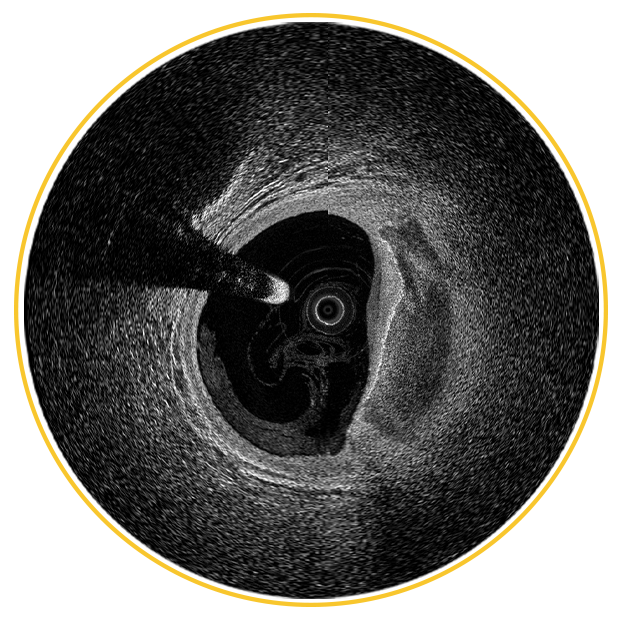

DeepOCT+NIRS: Uniting depth, resolution, and plaque characterization.

Engineered to visualize the EEL, detect full calcium thickness, and confidently image large vessels including left main.